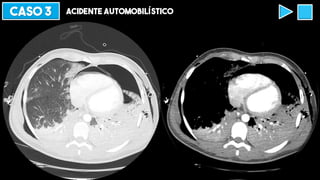

CASO 3 ACIDENTE AUTOMOBILÍSTICO